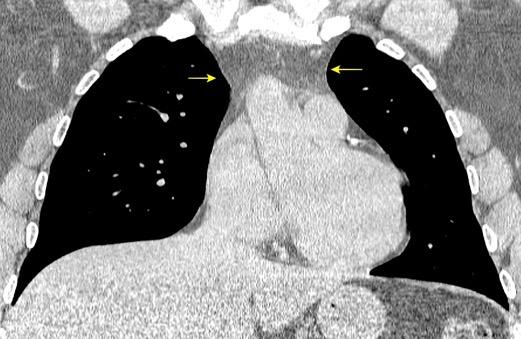

136. PERLAS NEGRAS, SIGNO DE LAS

Ramana. RV et al. The “Cluster of black pearls” sign of sarcoid lymphadenopathy: a new sign on thin-section contrast-enhanced multidetector CT. Clinical Radiology 2017